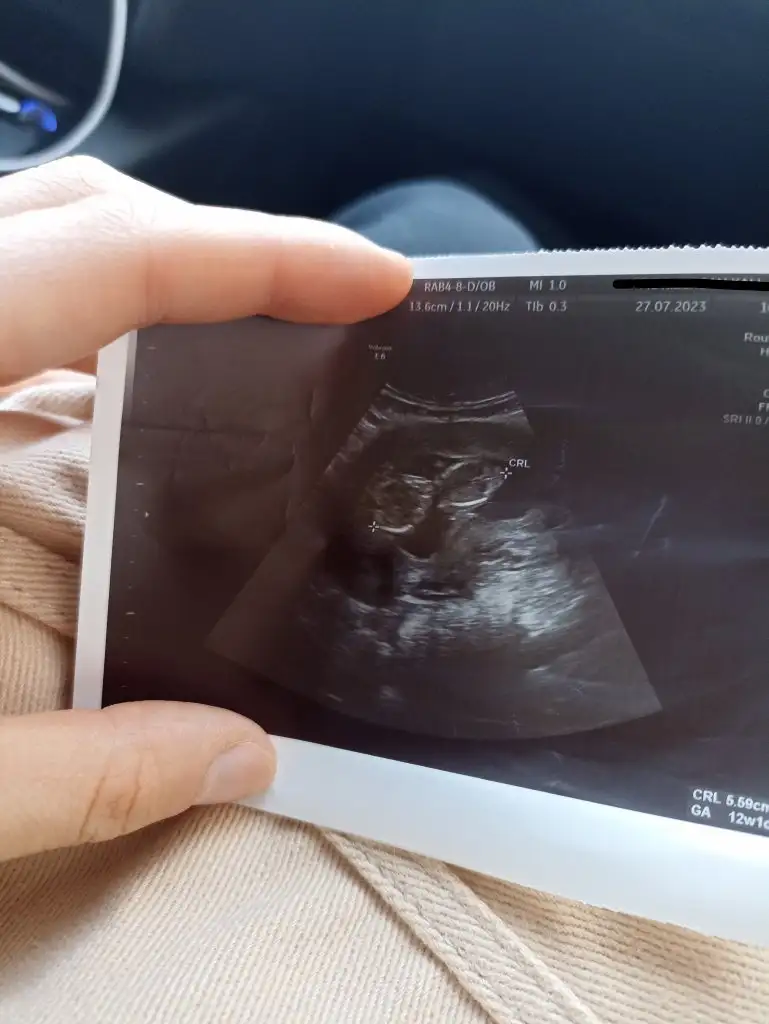

Kızlar banada tahminde bulunurmusunuz 12+5

Çok dikkatli şekilde baktım. Sivri çene için her ne kadar kız deseler de, nub hafiften yukarı bakıyor ve bu da erkek olduğunu gösteriyor. Sivri çene olup erkek olanını da görünce çeneye göre yorumlamak sanırım mantıklı gelmiyor bir yerden sonra, ama kız çıkarsa da nub belki pozisyonundan ötürü hafiften yukarı doğru bakıyormuş gibi çıkmış olabilir. Fakat ben yinede bebeğinizin erkek olduğunu düşünüyorum çünkü gerçekten de nub yukarı bakıyor.